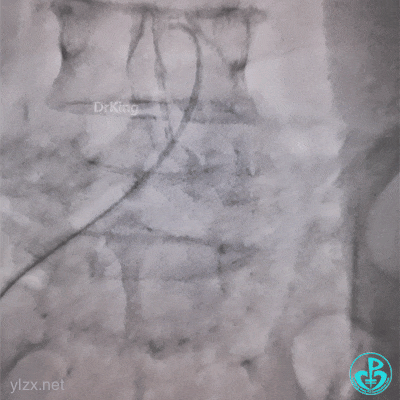

带的J-W转,突然血压没了,看下面,悲剧了。

糟糕,打折了,想解开,重新换管子。

结果上面又出问题。

管子反折,J-W根本无法通过。

10分钟过去了,怎么办?